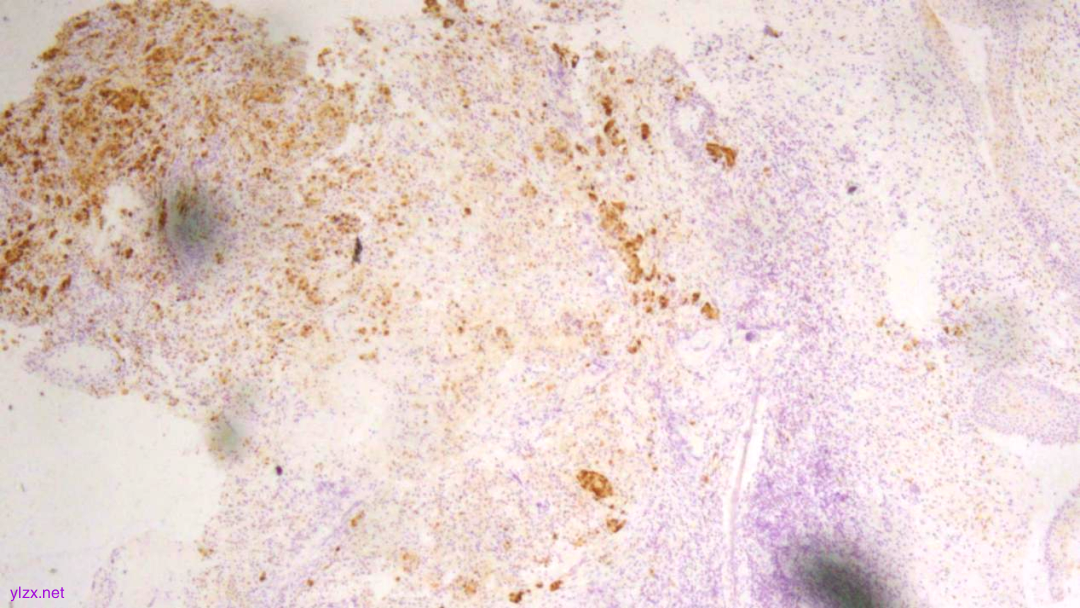

IHC结果:

P120(浆+),P16(灶+),P53(野生型表达),Her2(1+),CK7、GATA3、GCDFP-15、CK-H均(+),ER、PR、E-Cadherin、CK20均(-),Ki67(约5%+)

ER(-)

PR(-)

P120(+)

P120(部分+)

E-Cadherin(-)

GCDFP-15(弥漫+)

GATA-3(+)

CK7(弥漫强+)

Her2(1+)

Ki-67(散在+)

(宫颈2点、5点、10点活检组织及宫颈管搔刮组织)HE形态结合临床病史、免疫组化结果,符合乳腺浸润性小叶癌转移。